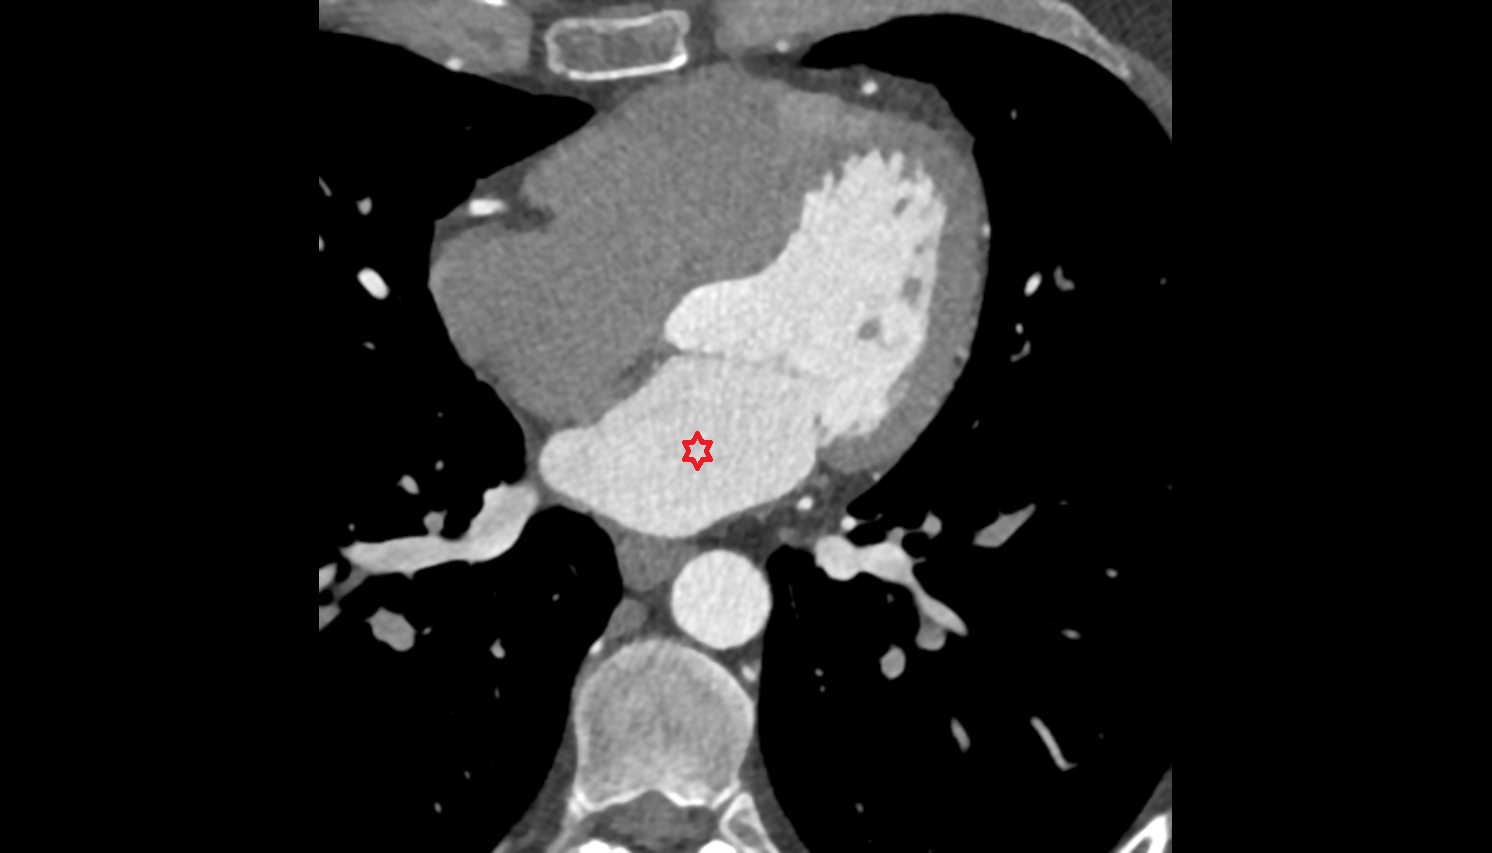

- Heart

- Left ventricle

- Right atrium

- Left atrium

- Right ventricle

- Interventricular Septum

- Aortic root

- Ascending aorta